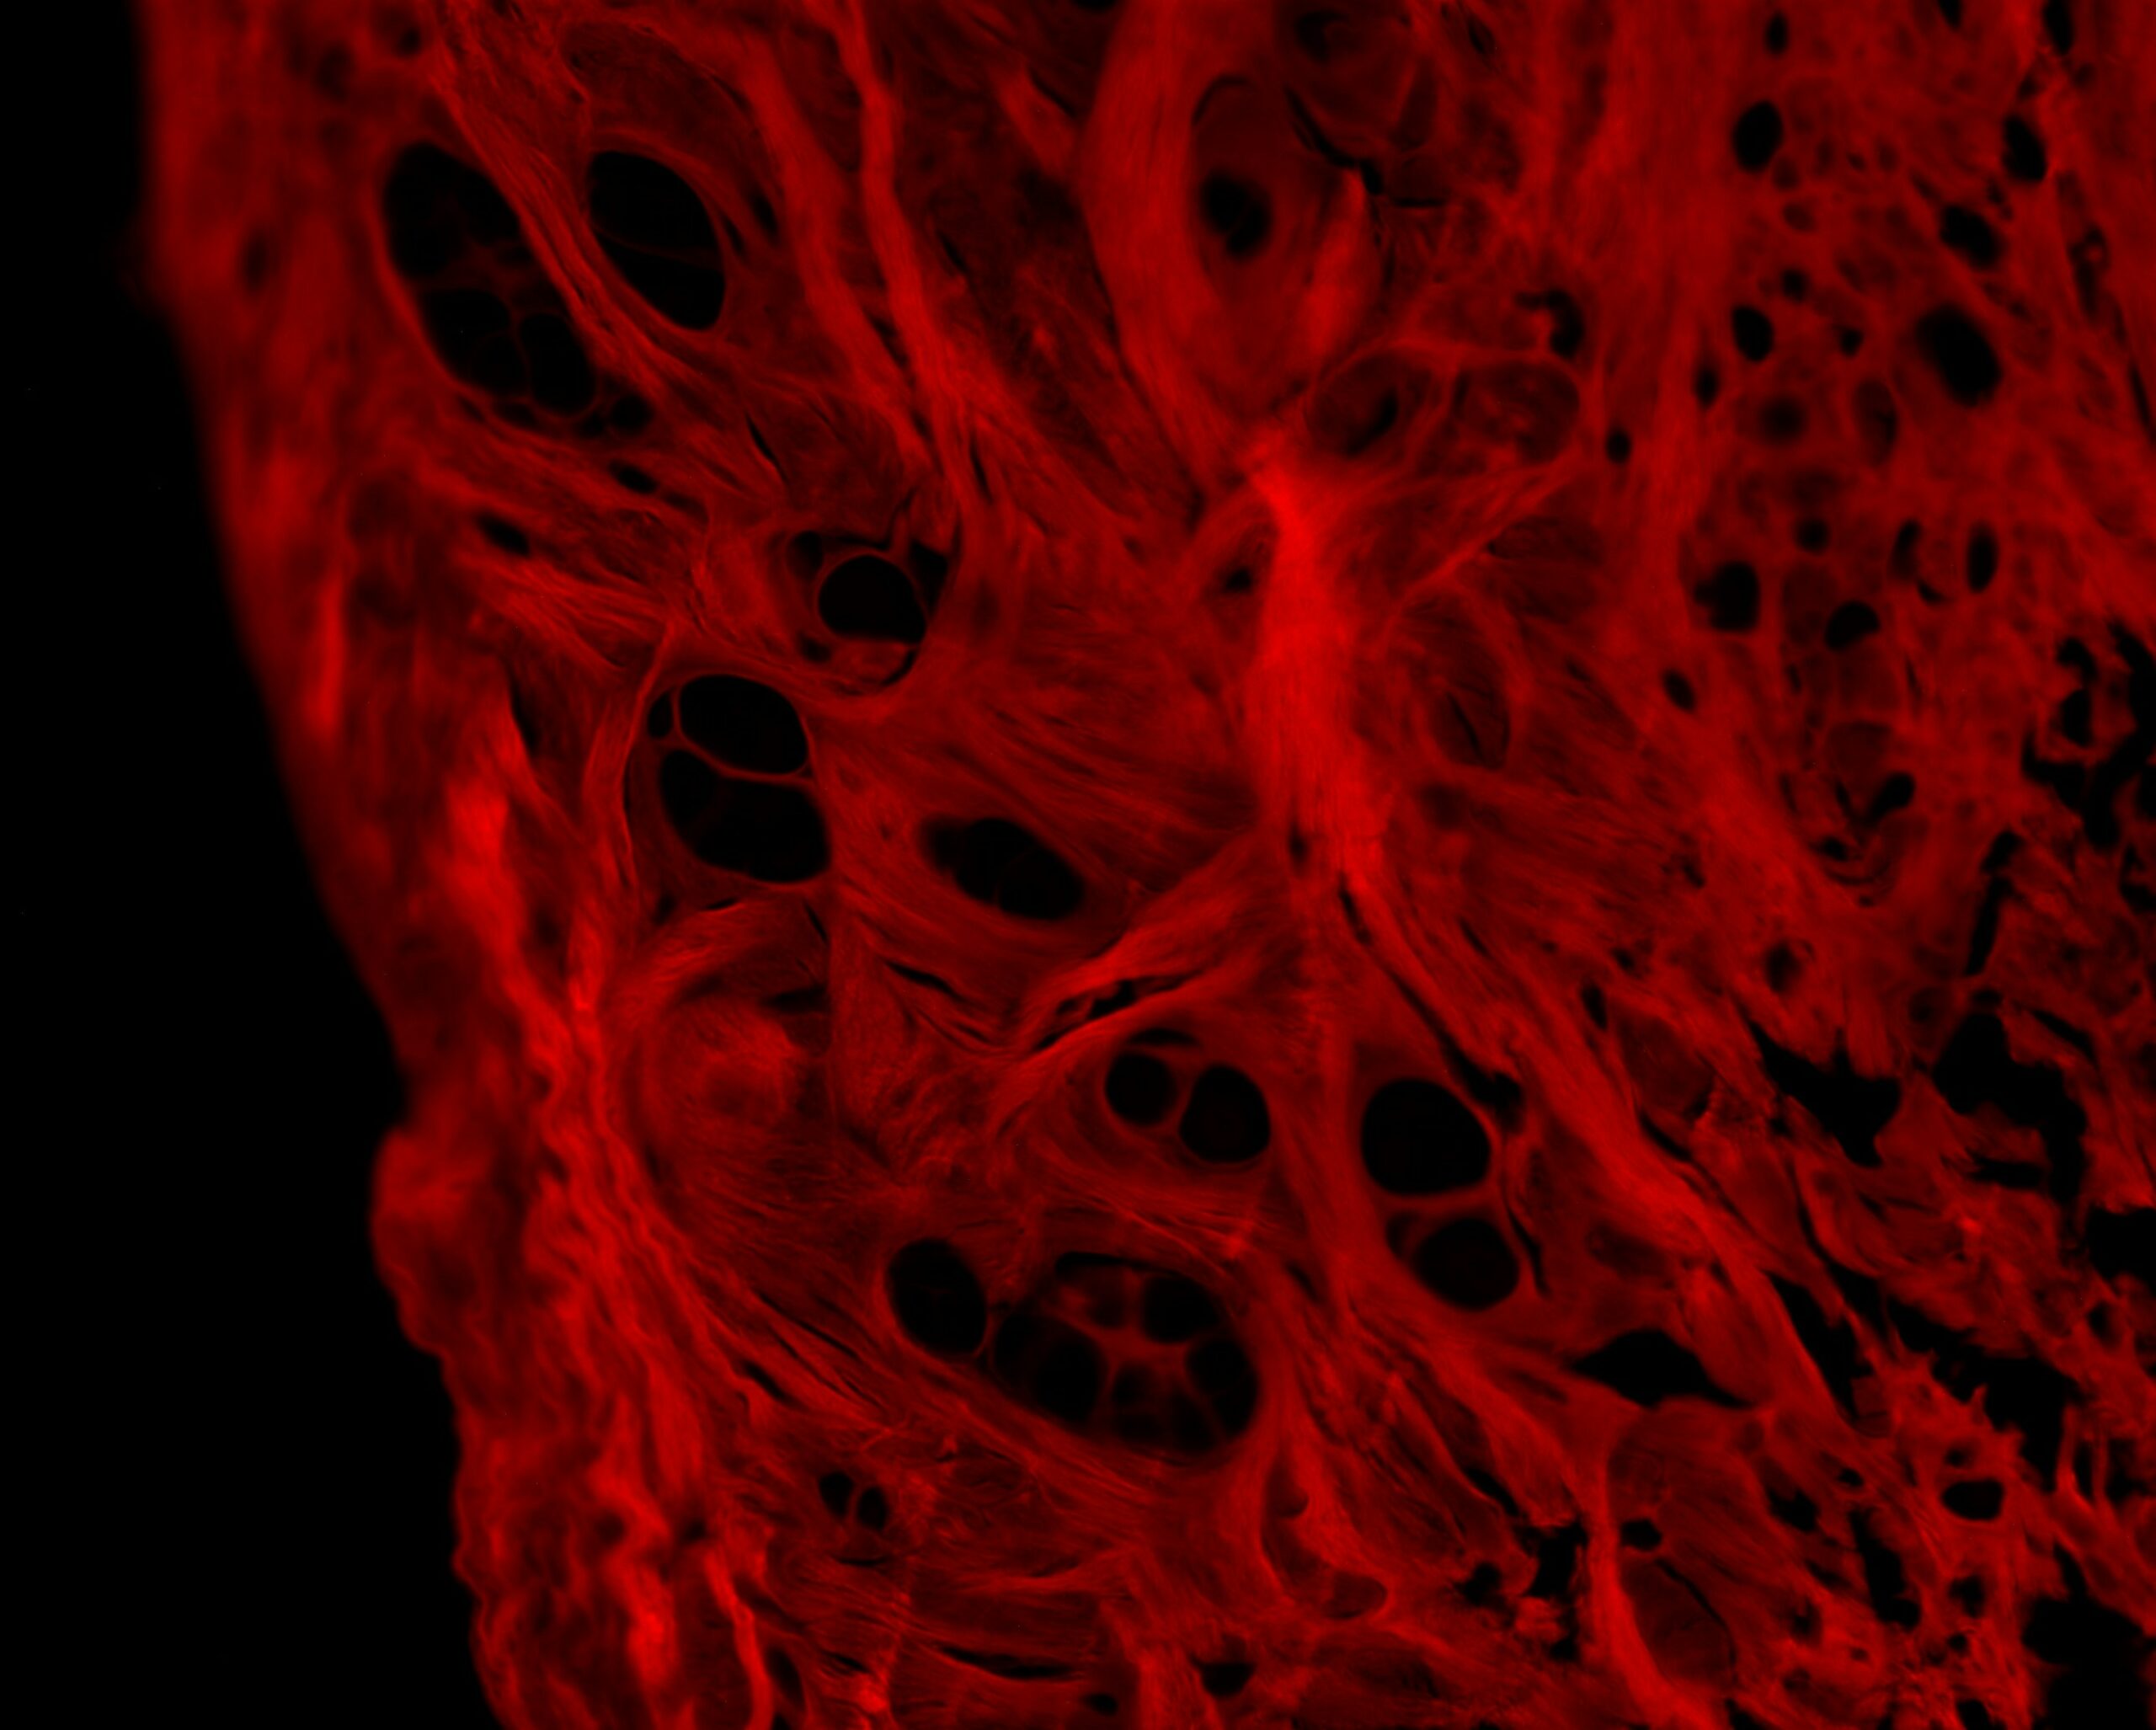

Scanning electron microscopy (SEM) is a revolutionary technique that allows us to obtain images of exceptional precision by studying